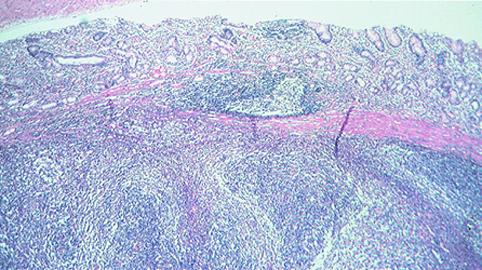

A case of gastric low-grade MALT lymphoma in which Helicobacter pylori eradication was ineffective and a gastrectomy was performed.

Malignant Lymphoma/Malignant lymphoma

Stomach/Body

Histology

submucosa